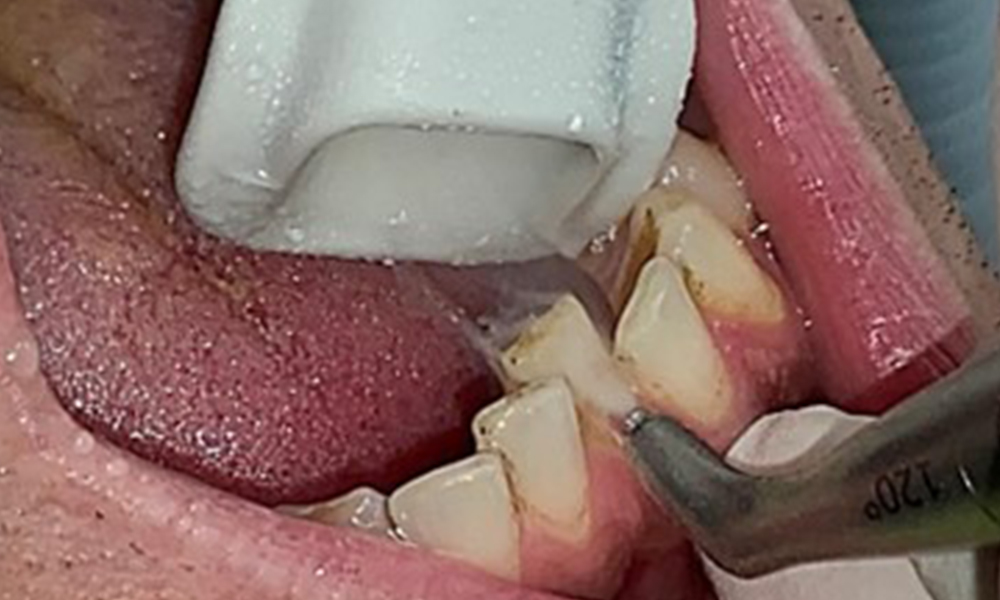

Instruction and motivation are important components of these appointments. Good home-based intraoral hygiene behaviour and understanding are important for patients. Plaque accumulation is particularly evident in the cervical regions (Fig. 8).

The arrows indicate plaque accumulations in the cervical region

Fig. 8: The arrows indicate plaque accumulations in the cervical region, © Dr R. Krapf

These must be discussed with the patient, and improvements to the teeth-brushing technique must be practised. A soft toothbrush attachment is recommended for home-based intraoral hygiene due to the presence of erosions and attritions.